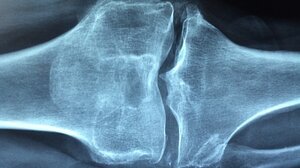

Αύξηση καταγράφουν τα κατάγματα σπονδυλικής στήλης σε παγκόσμιο επίπεδο ΥΓΕΙΑ 07.06.2022Αύξηση καταγράφουν τα κατάγματα σπονδυλικής στήλης σε παγκόσμιο επίπεδο